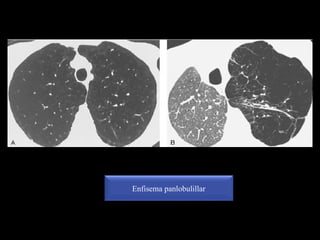

Panlobulillar (panacinar)

. Disminución de la atenuación pulmonar y del tamaño de los vasos

. Carecen de pared

Enfisema panlobulillar